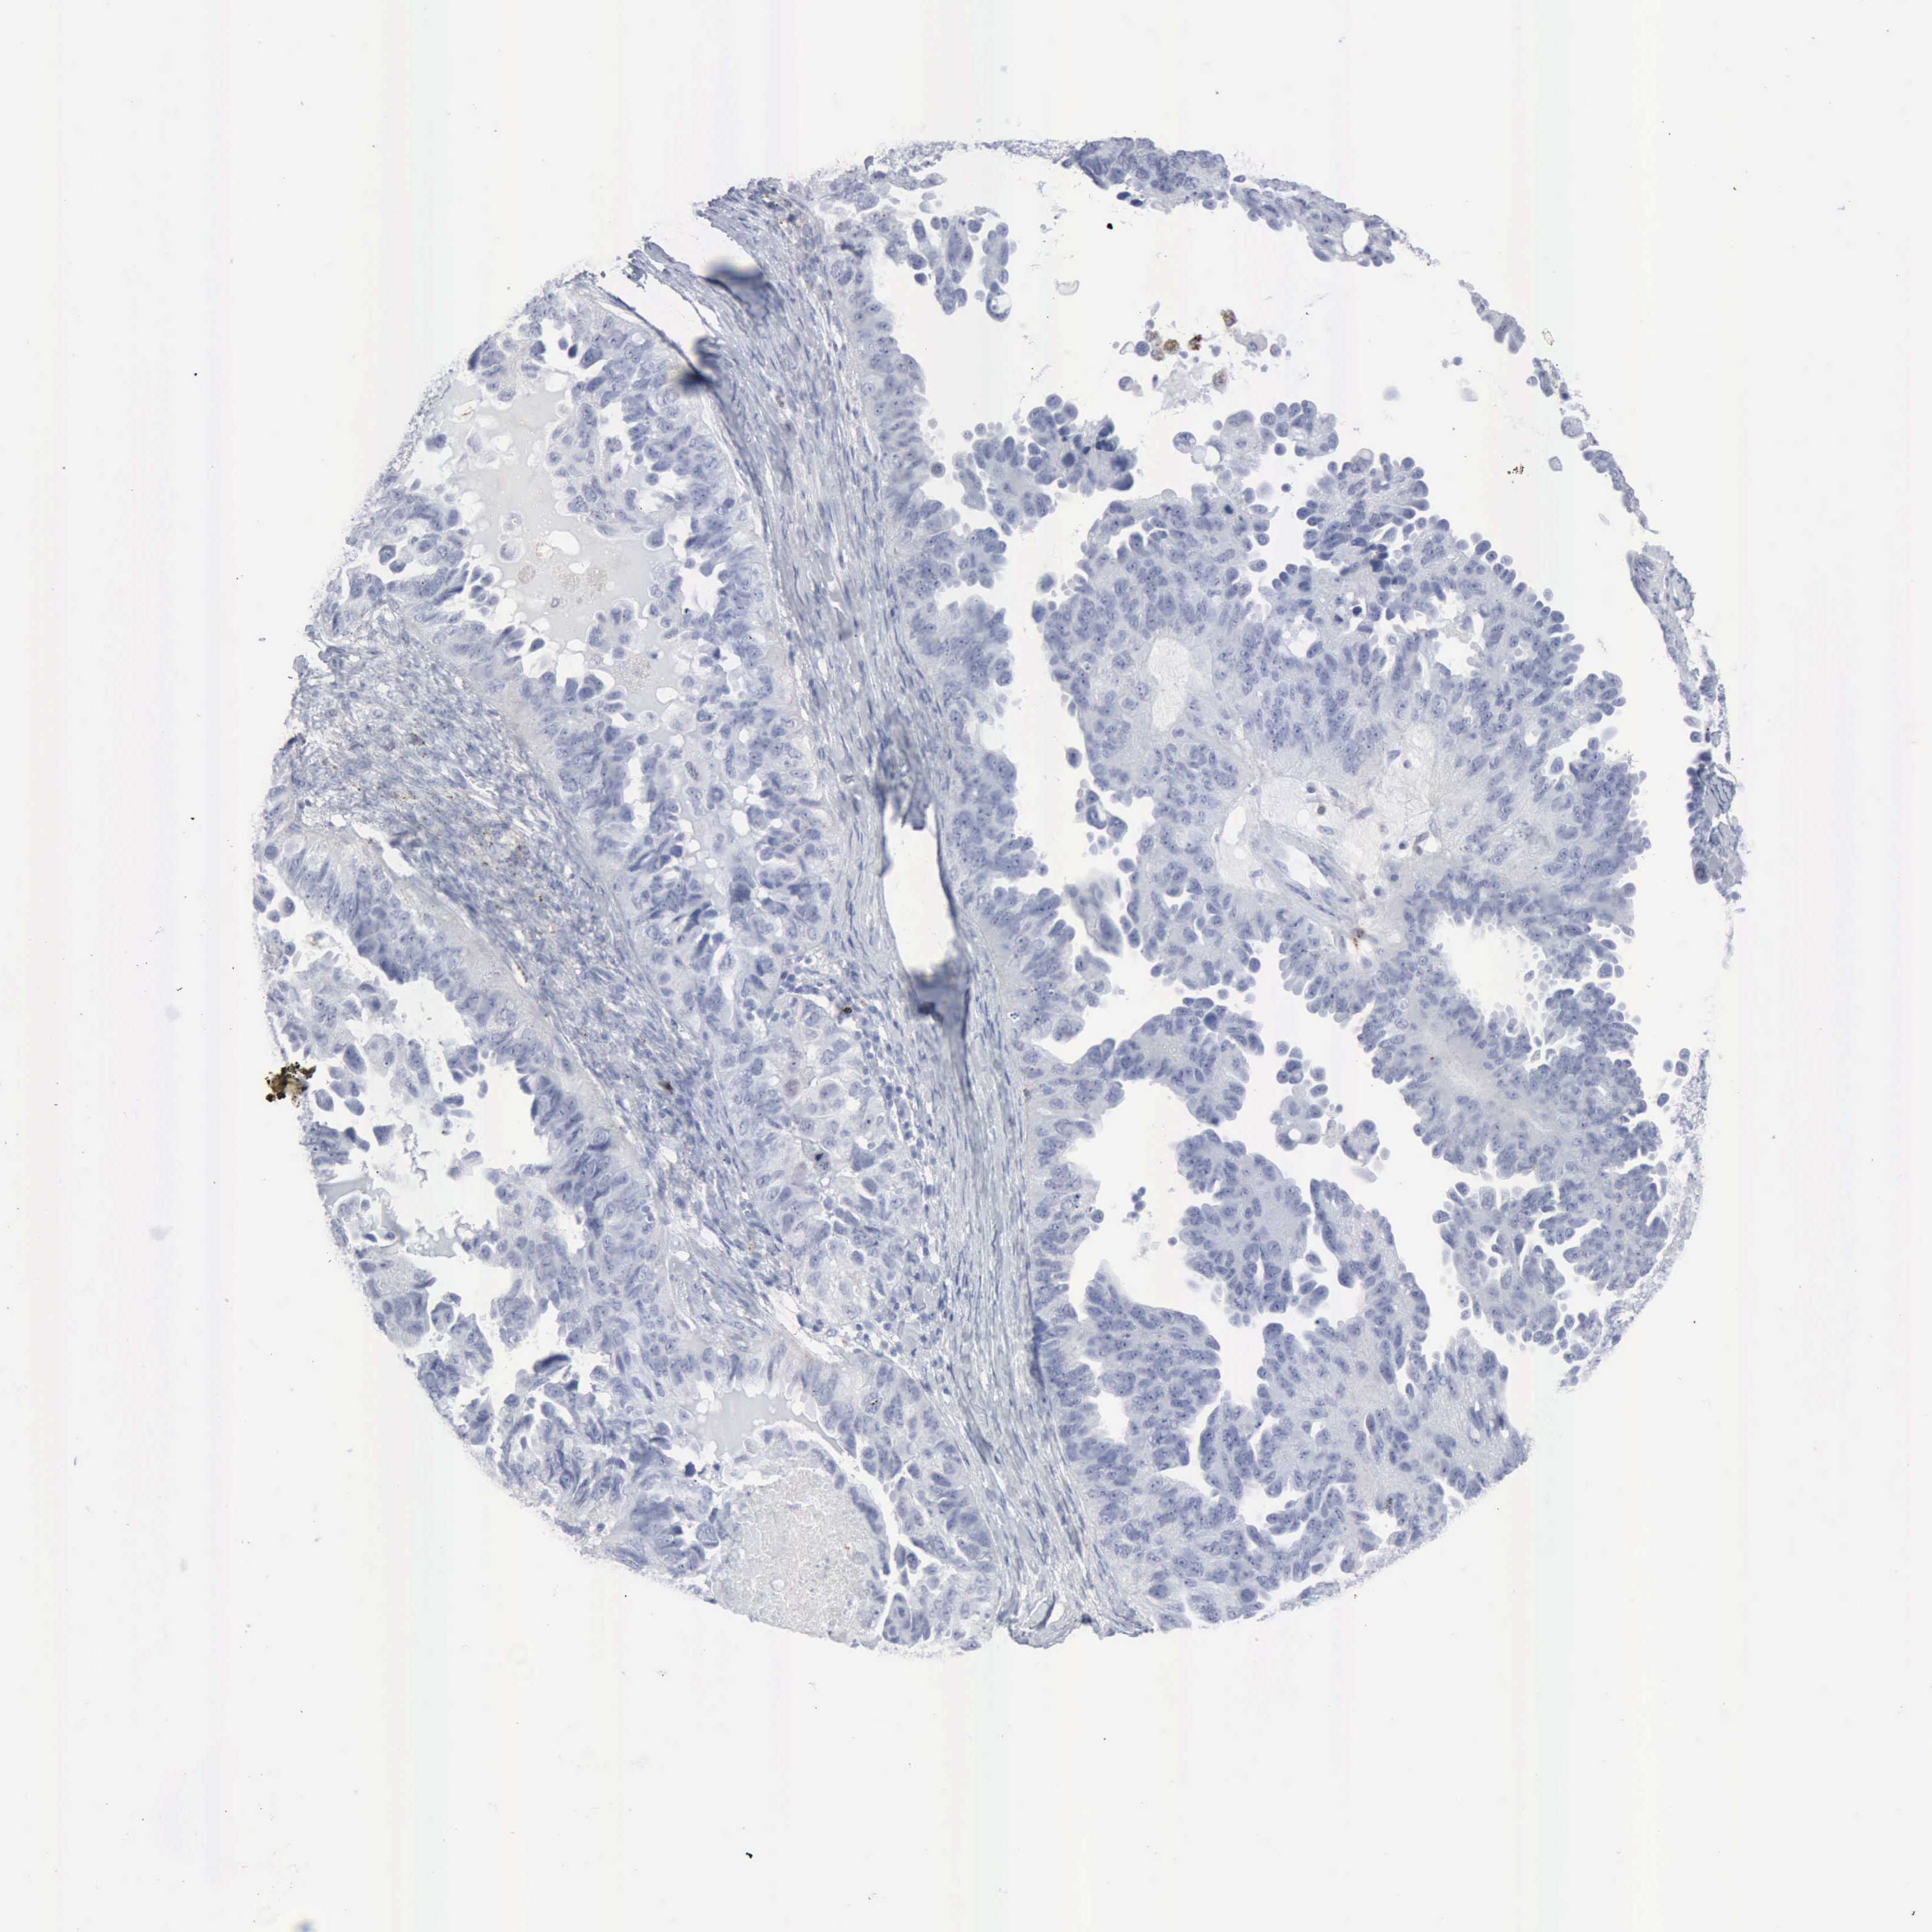

OVARIAN CANCER - Protein expressioni

A mouse-over function shows sample information and annotation data. Click on an image to view it in a full screen mode. Samples can be filtered based on level of antibody staining by selecting one or several of the following categories: high, medium, low and not detected. The assay and annotation is described here.

Note that samples used for immunohistochemistry by the Human Protein Atlas do not correspond to samples in the TCGA dataset.

Antibody stainingi

Antibody staining in the annotated cell types in the current human tissue is reported as not detected, low, medium, or high, based on conventional immunohistochemistry profiling in selected tissues. This score is based on the combination of the staining intensity and fraction of stained cells.

Each image is clickable and will lead to virtual microscopy that enables deeper exploration of all samples and also displays staining intensity scores, fraction scores and subcellular localization as well as patient and tissue information for each sample.

Antibody HPA000237

Antibody HPA000966

Staining

High

Medium

Low

Not detected

Intensity

Strong

Moderate

Weak

Negative

Quantity

>75%

75%-25%

<25%

None

Location

Nuclear

Cytoplasmic/membranous

Cytoplasmic/membranous,nuclear

Cystadenocarcinoma, mucinous, NOS

Carcinoma, endometroid

Cystadenocarcinoma, serous, NOS